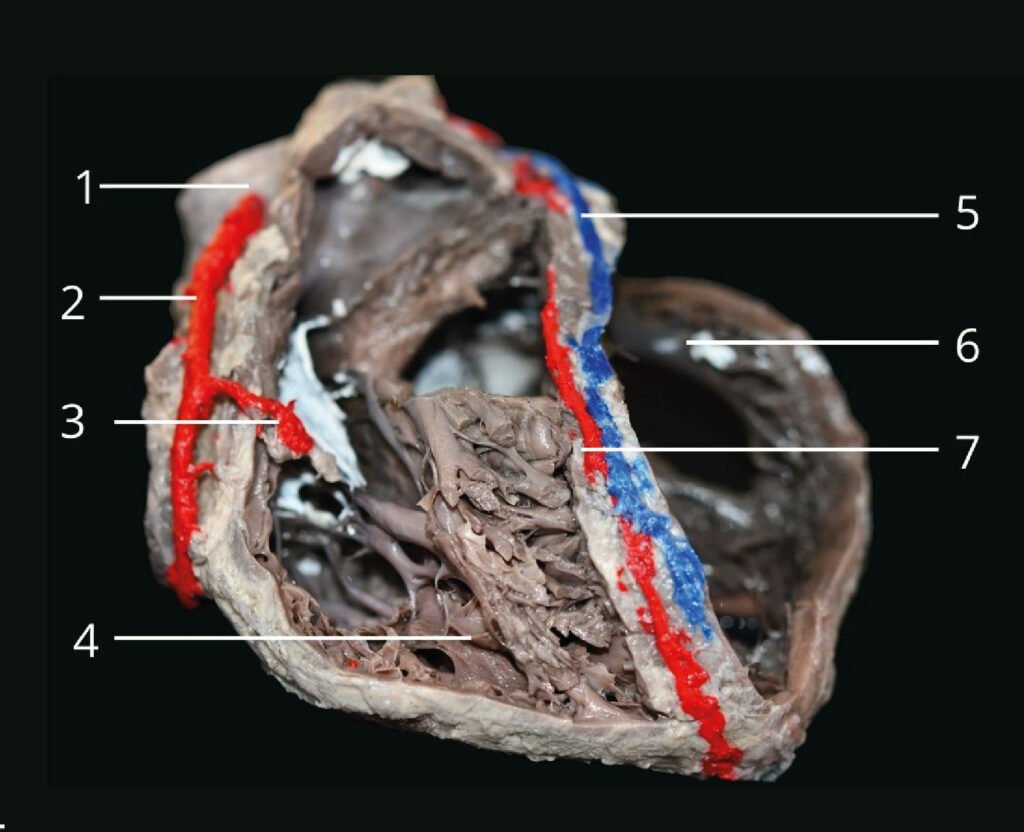

Museo.

Encontrarás los preparados de nuestro laboratorio en el museo de Anatomía J. J. Naón, Facultad de Medicina, Universidad de Buenos Aires, con su descripción.

Encontrarás los preparados de nuestro laboratorio en el museo de Anatomía J. J. Naón, Facultad de Medicina, Universidad de Buenos Aires, con su descripción.